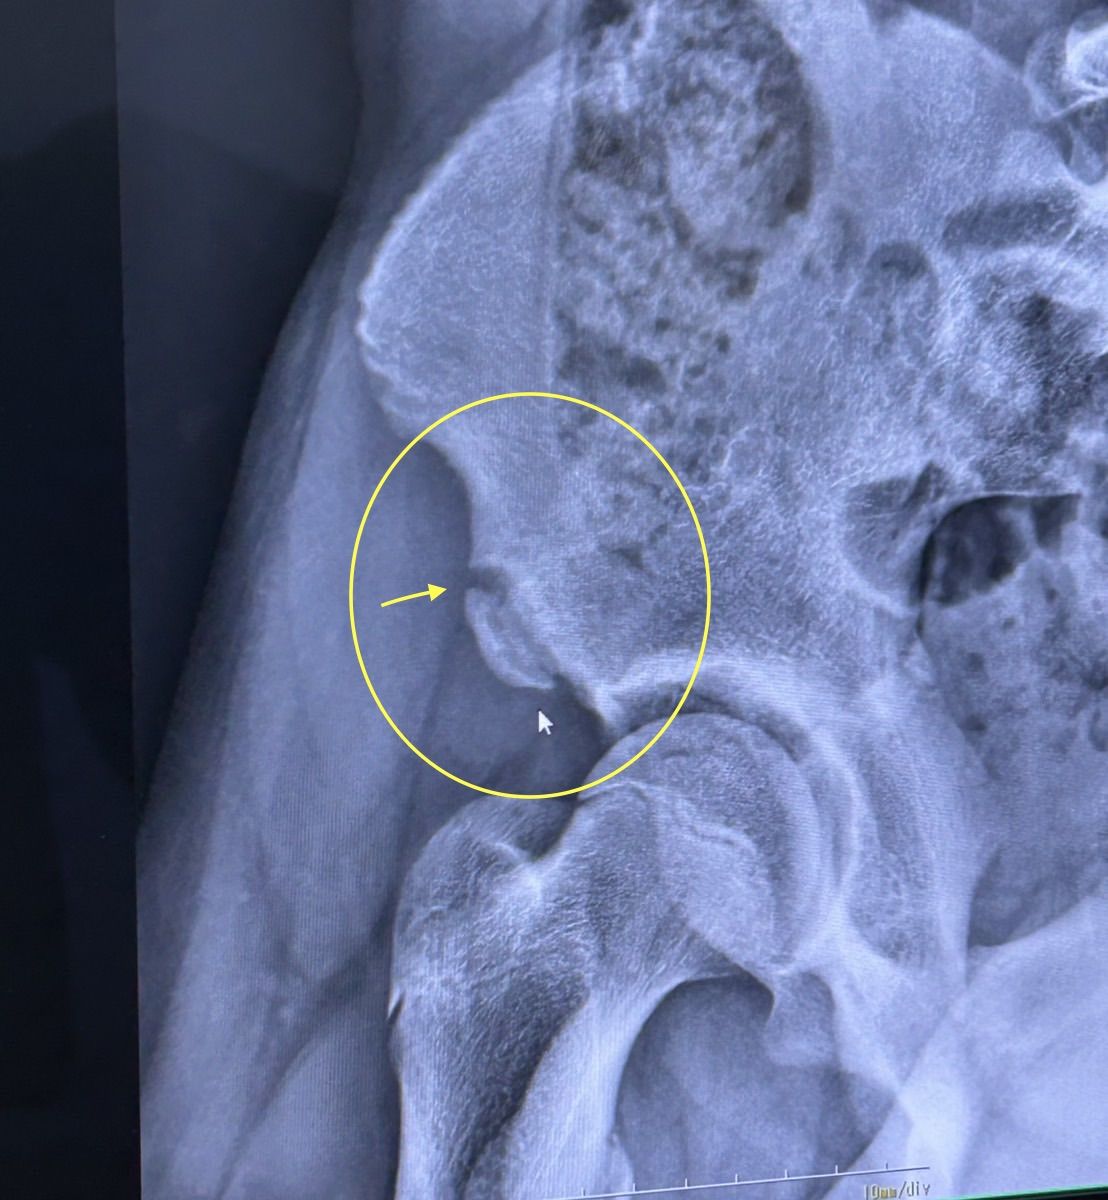

• 【骨盤の骨折・下前腸骨棘骨折の超音波治療(リーパス)の症例】茅ヶ崎市でおすすめの整骨院・接骨院の症例 No182

患者データ:10代、男性、学生、サッカークラブ、既往歴:オスグッド・シーバー病・成長痛・肉離れ

疑われる疾患と主訴:右股関節の痛み、股関節が痛くて走れない。サッカーができない。

動機:股関節の痛みが出現し日に日に痛みが増してきたため来院。と回答。

エピソード:中学生になり、上位チームの練習に参加、レギュラーにも選ばれオーバーワーク気味であった。ダッシュの練習でスタートした際に激痛が走り負傷。走行不可・キック不可となる。歩行は通常のため、様子を見ていた。

NEEDS判定:修復サイクルを促進させ癒合機関の短縮。患部外トレーニングを並行して行い、筋力・持久力の低下を最小限に抑えることができた。

患者様からのADVICE:歩けていたので油断していた。無理をして長期間の療養になるところでしたので助かりました。怪我やスポーツの痛みは相談してみてください。と回答。

期間と回数:11週間、45回(超音波治療はまめに通院し、リハビリは1〜2回/W

施術内容:全身機能検査、病態検査、生活リズムと食事のアドバイス、セルフケア、体幹トレーニング、EMS、高周波治療機器、MCR、セルフエクササイズ

画像と動画:

考察:負傷前の練習強度やセルフケアの状況、生活環境の聴取、発生機序から推測。歩行可能な場合もあるのでこのようなケースは検査が必要である。